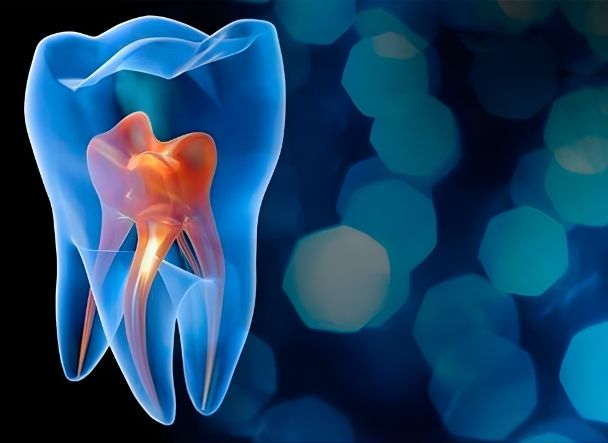

Endodoncia

Devitaliza el nervio y trata los conductos para conservar la pieza en casos de caries profundas, infecciones o traumatismos.